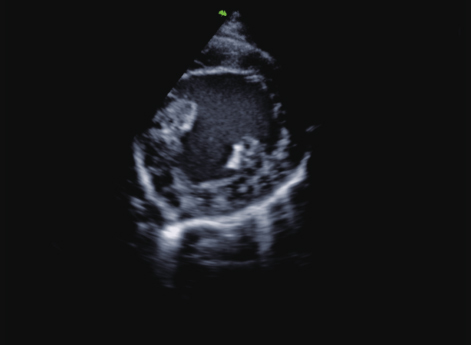

可以将M型的取样线任意方向、任意位置移动取样,方便对某些由于病变导致心脏位置异常的病例进行M型扫查分析。